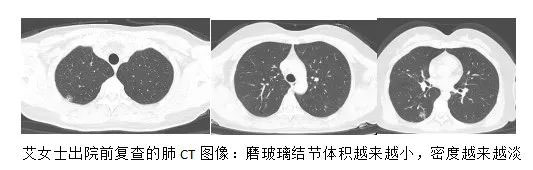

李某觉得丈夫的话很有道理,于是抱着最后一丝希望,来到了首都医科大学附属北京胸科医院影像专家门诊。侯代伦教授严肃认真地看了好一会儿艾女士的胸部CT片,多年的临床实践和潜心钻研,让他练就了一双火眼金睛,在了解了大致病史后他微笑着说:“你这不是肺癌,但长的太像肺癌了,双肺多发的磨玻璃结节边界都很模糊,这要么是特殊感染,要么是过敏,先消炎看看,或者做个气管镜刷检取证,建议入院完善相关检查。”侯主任自信的话语给了艾女士一家新的希望,当即决定要在北京胸科医院进行进一步检查及治疗。经过我院呼吸科半个月的抗炎治疗后,艾女士肺内的磨玻璃结节体积越来越小,密度越来越淡,艾女士精神状态明显好转,经医生评估可出院休养,艾女士回到了老家哈尔滨休息,等待病灶的继续吸收。

3月16日,艾女士再一次来到了北京胸科医院复查肺CT,好消息传来,结节大部分已经消失,仅剩右肺下叶隐约可见到淡淡的小斑片影。